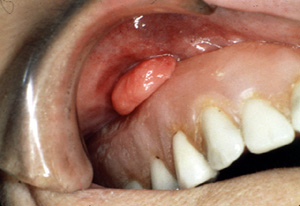

| Este épulis

fisurado involucra el vestíbulo

de la mandibula anterior. Aunque no esté la dentadura postiza que

produce dicha lesión, hace pensar en una asociación íntima entre la prótesis

desaptada y la lesión. Los rasgos clínicos también hacen pensar en la

posibilidad de malignidad. En todos los casos, se indica una biopsia

para el diagnóstico preciso.

fisurado se encuentra en una localización no habitual, en la

almohadilla retromolar.

Este

ejemplo extraño parece estar originando

porque la dentadura postiza irritaba la mucosa vestibular. |